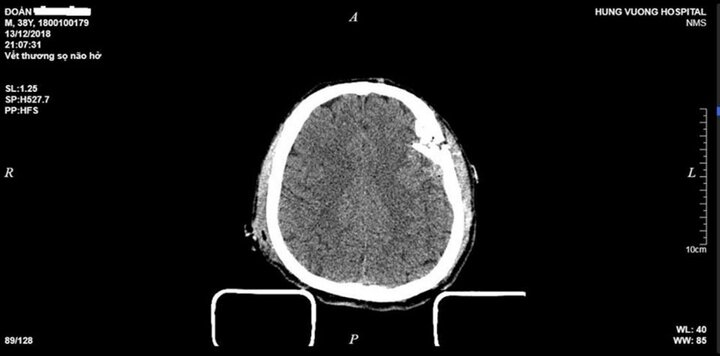

Bệnh viện Đa khoa Hùng Vương (Phú Thọ) vừa cứu sống nam thanh niên lâm vào trạng thái lơ mơ, vật vã, vỡ lún xương sọ và dập não.